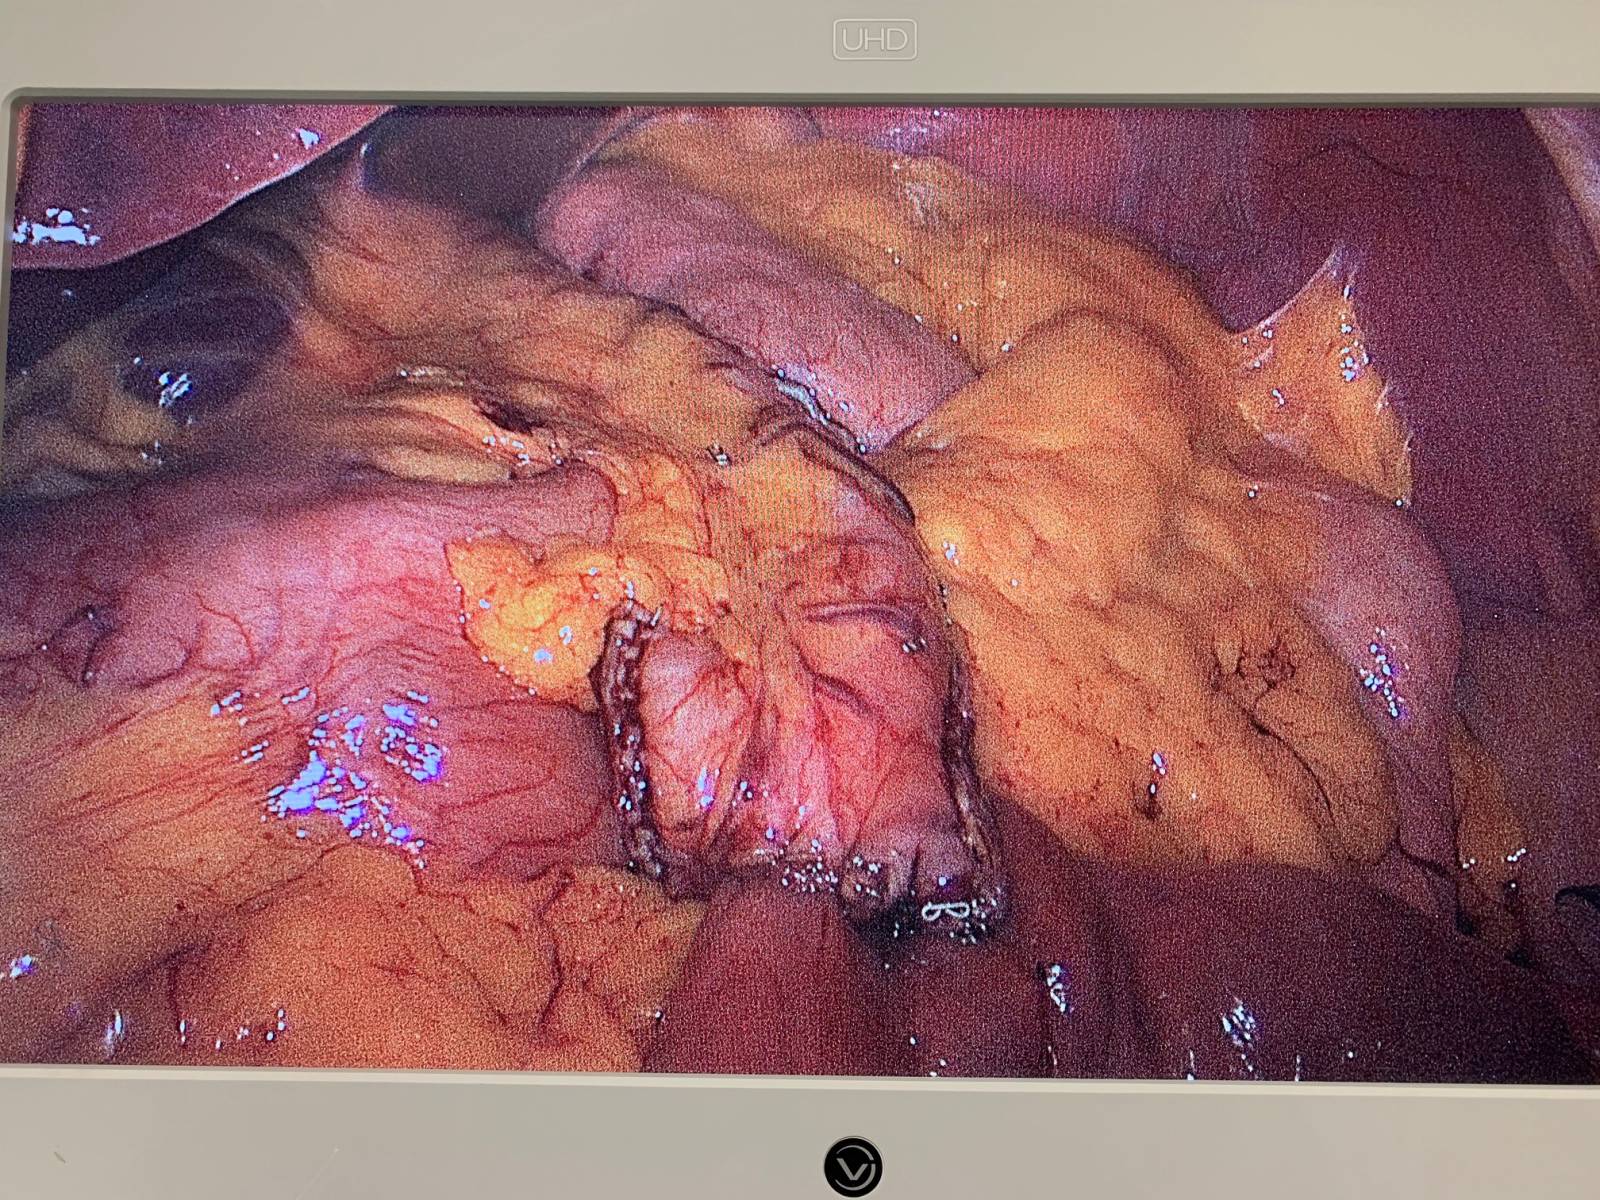

1.	Traitement chirurgical des complications fonctionnelles après sleeve : la conversion en bypass gastrique en Y.

Au cours de cette dernière décennie, la gastrectomie longitudinale laparoscopique  (LSG) ou Sleeve est devenue la procédure bariatrique la plus réalisée en Fr...

Technique Chirurgicale du OAGB: recommandations du groupe MUST suite à la publication de Kamal Mahawar

Les chirurgiens digestifs du groupe MUST à Paris valident les recommandations du Dr Kamal Mahawar sur la technique de confection de la poche gastrique pour u...